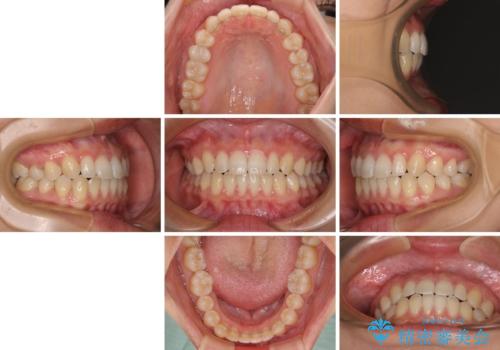

隙間だらけの歯列 インビザラインで改善

空隙歯列(すきっ歯)は、舌の突出癖をある程度改善できたとしても、後戻りにより隙間が開きやすいと言われています。

裏側から細いワイヤーで保定するとともに、睡眠時のマウスピース装着を徹底していただくことで、後戻りを最小限にとどめます。